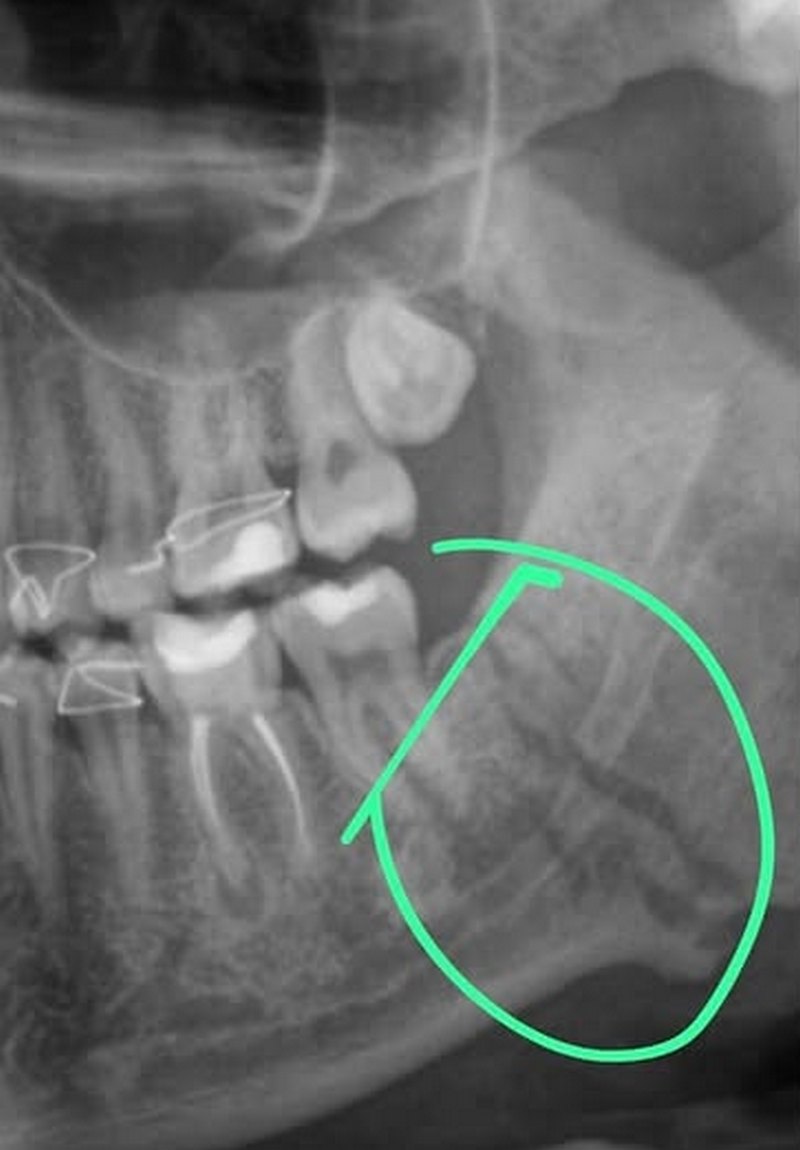

Врачи диагностировали у пострадавшего: двойной перелом челюсти, черепно-мозговую травму, сотрясение мозга и повреждение глаза. Потерпевший, по его словам, до сих пор не может нормально есть и говорить.

- Сегодня мне дали заключение экспертизы: "средняя степень вреда здоровью", с чем я категорически не согласен. В заключении игнорируется сотрясение голового мозга, черепно-мозговая травма и повреждение глаза. Я подал официально возражение и хочу, чтобы их привлекли согласно статьи 106 УК РК (умышленное причинение тяжкого вреда здоровбью, - говорит пострадавший.